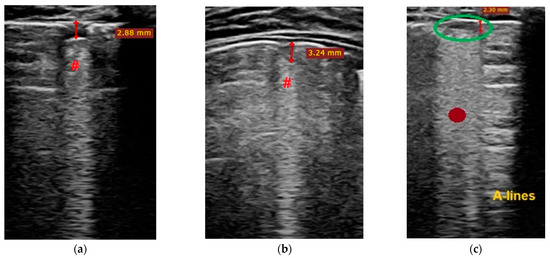

- Transverse physiologic A-lines that depict healthy parenchyma;

- Isolated/sparse vertical B-lines are equivalent to interstitial edema;

- Confluent vertical B-lines correspond to alveolar edema;

- Subpleural/peripheral consolidations;

3.3. Lung ultrasound investigation, score and correlation

| LUSS = 0 Points | LUSS = 1 Point | LUSS = 2 Points | LUSS = 3 Points |

| Normal/physiological A-lines | More than 2 B-lines (sparse B-lines) with associated pleural abnormalities | Coalescent or confluent B-lines | Large peripheral consolidation (wider than 1 cm) in association or not with air bronchogram |

| One or two B-lines per intercostal space | ‘White-lung’ aspect or small peripheral consolidation (smaller than 1 cm) |